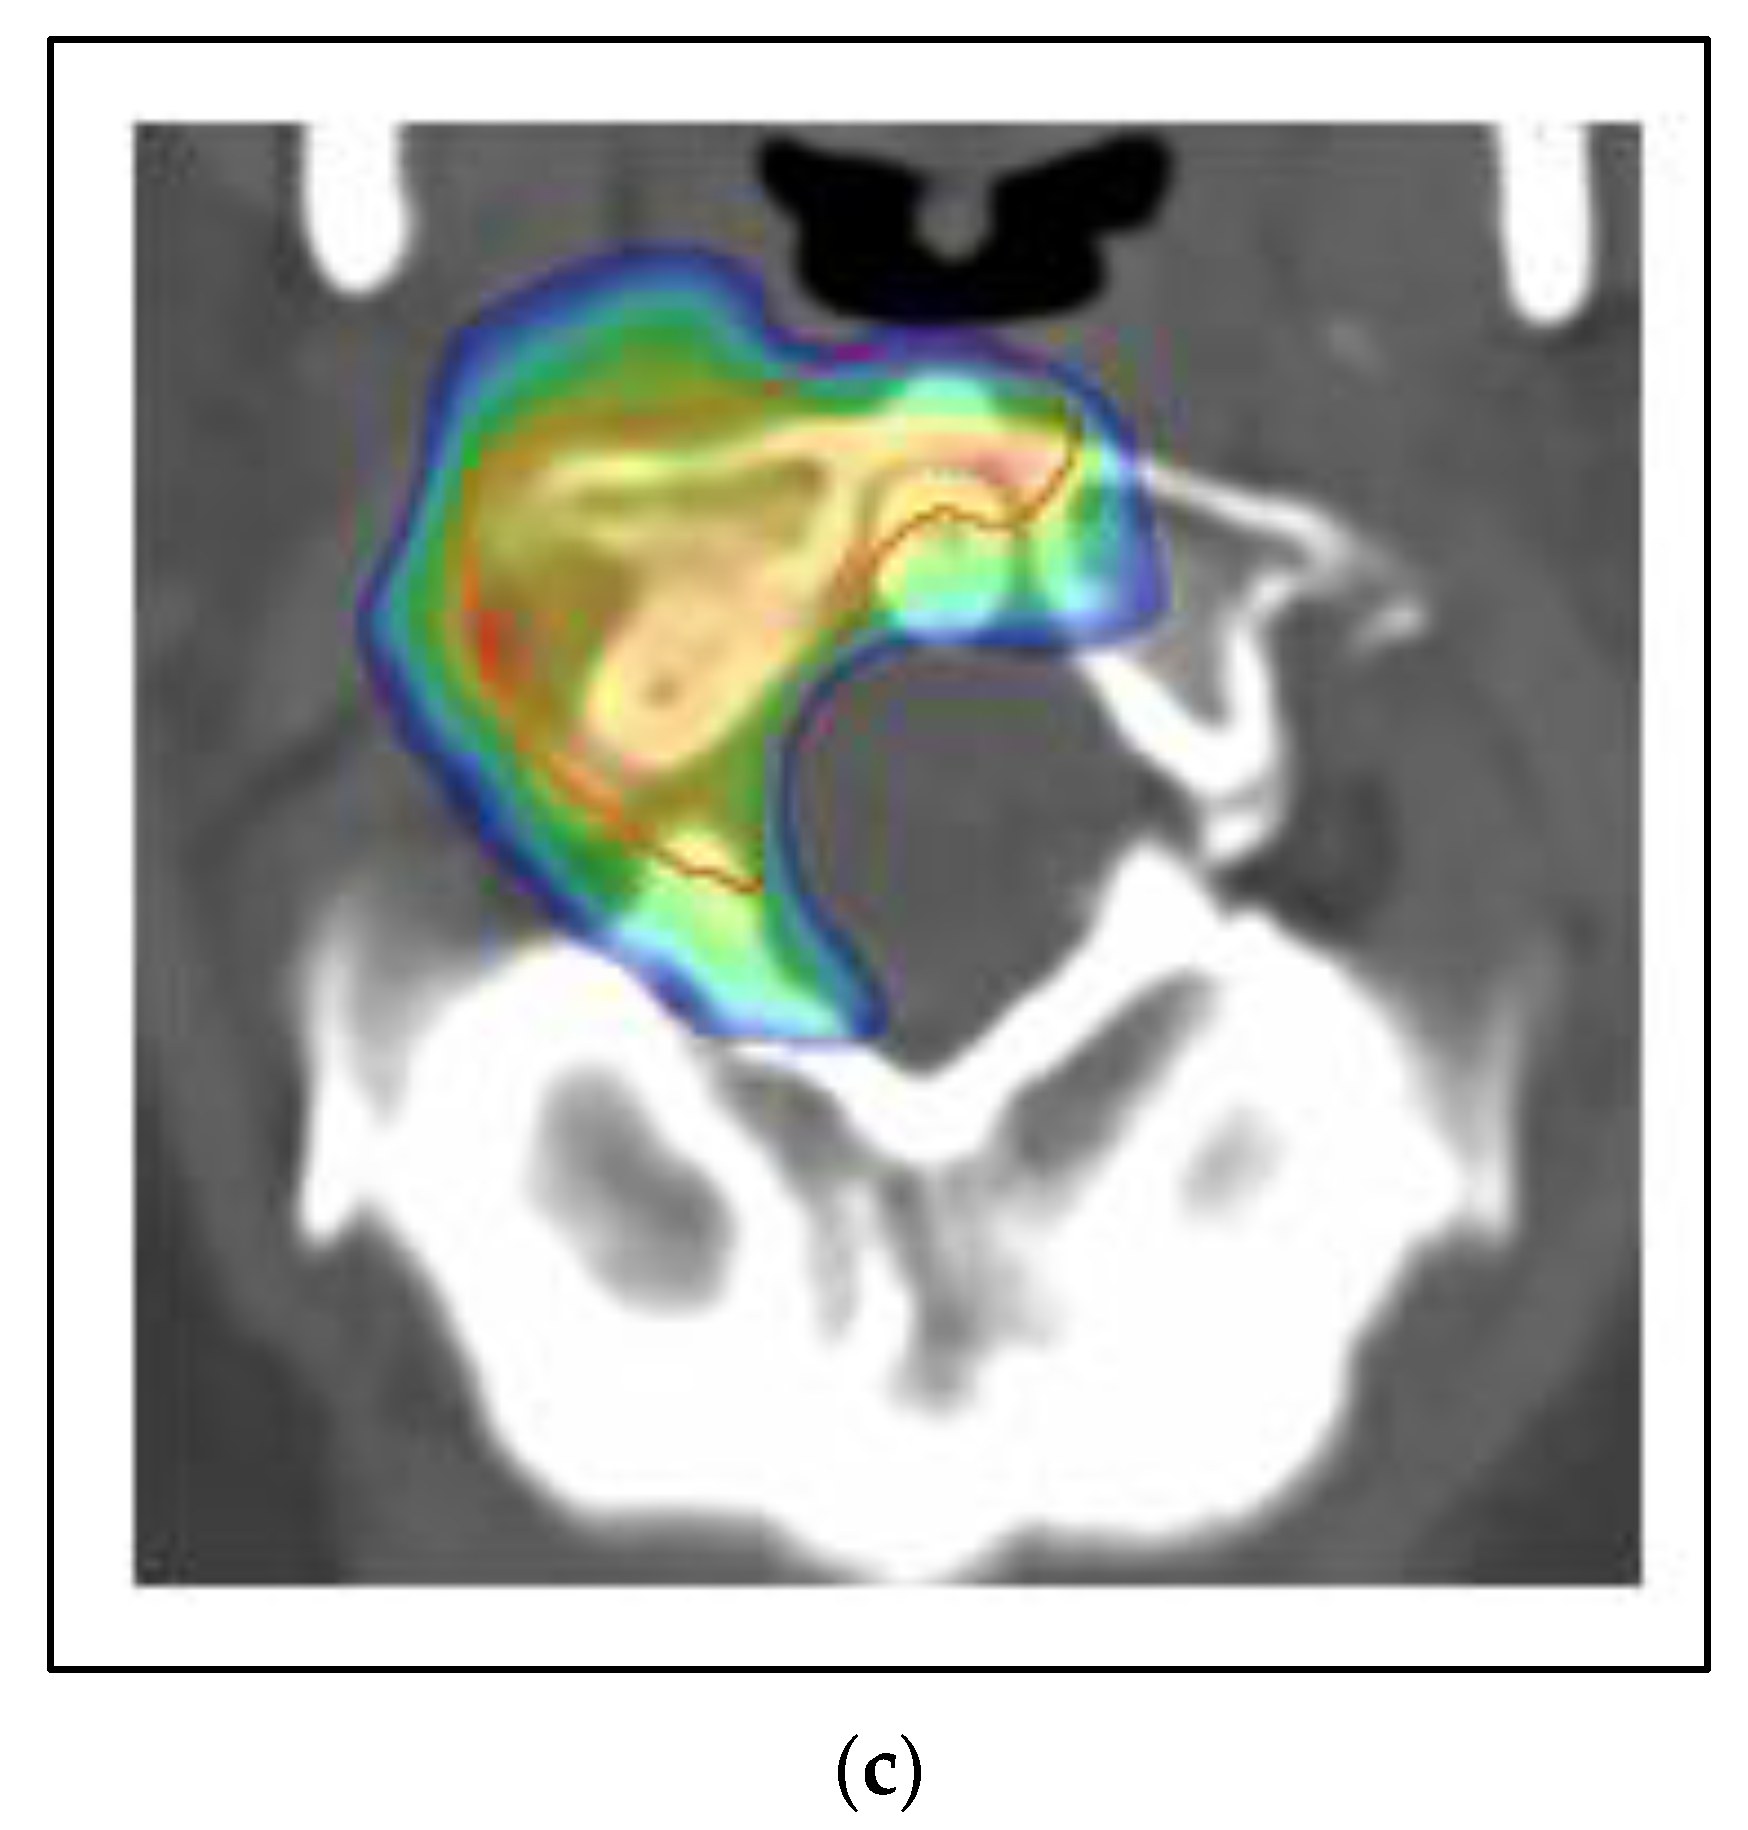

The majority of the patients in the BR002 trial had metachronous oligometastases after the initial local-regional treatment. Figure 4 shows a case of a 75-year-old woman with a metachronous presentation of oligometastatic breast cancer to the liver. Her initial node positive breast cancer was ER positive, PR positive, and HER2 negative and treated more than five years earlier with mastectomy, postmastectomy radiation, chemotherapy and five years of tamoxifen. She developed abdominal symptoms and elevated liver function tests and imaging showed two lesions of the liver, 2.2 cm and 0.8 cm. A liver biopsy was positive for metastatic breast cancer of the same receptor pattern as the original primary. She was treated with SBRT to both liver lesions, followed by an aromatase inhibitor and remains without evidence of disease progression four years later.

Figure 4. Case 3: Metachronous oligometastases. A 75-year-old woman presented with metachronous metastatic breast cancer to the liver over 5 years from her initial treatment. She was treated with SBRT to both liver lesions. MRI (a) and PET/CT (b) imaging of one of the two liver metastases. (c) A colorwash image superimposed on a radiation planning CT showing the dose from SBRT to 50 Gy in 5 fractions using proton beam radiation. Representative images showing a complete response on MRI (d) and PET/CT (e) 4 years after SBRT treatment.